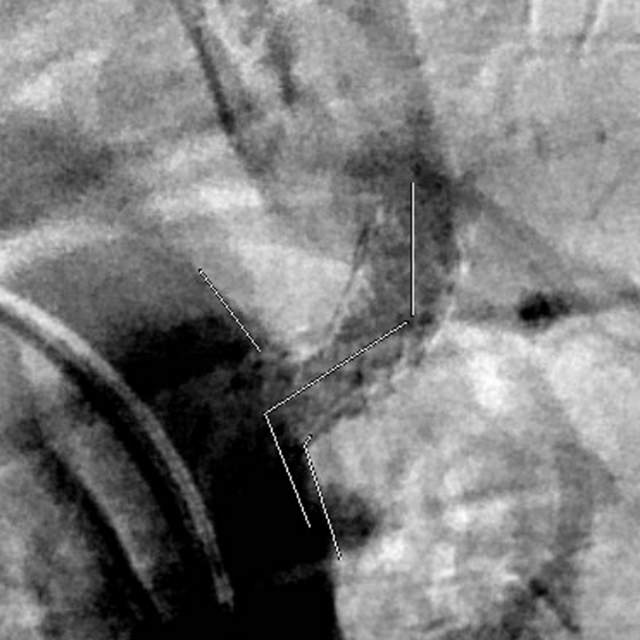

最近,儿子带老人家过来复查,检查发现右侧椎动脉起始部的狭窄越来越重,和9个月前相比,简直判若两人(管),左侧椎动脉又先天发育不好……,看来保守治疗吃药不太行,还得需要外科干预